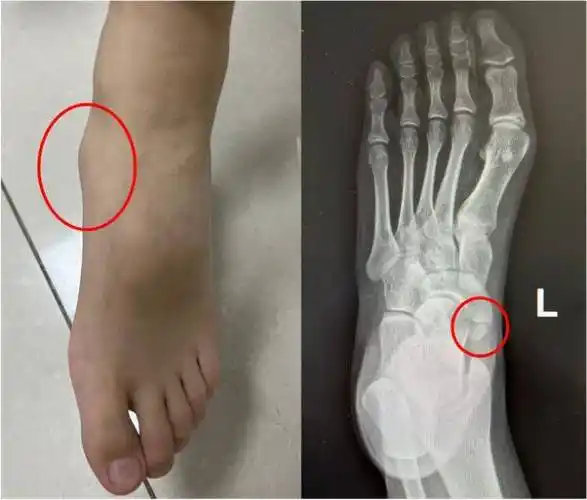

今日门诊遇见一位9岁患儿,主诉双足内侧面疼痛约20天,以右足 - 抖音

孩子扁平足,最近说双脚外侧突出来的骨头痛,带去看小儿骨科拍片子